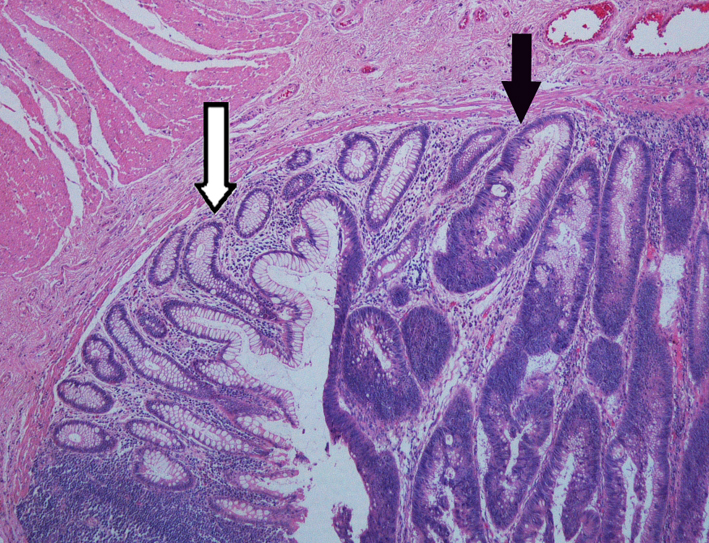

2.Adenocarcinoma of the colon